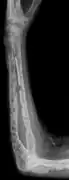

-

X-ray of the forearm, with lytic lesions -

Femur with multiple myeloma lesions -

Same femur before myeloma lesions for comparison -